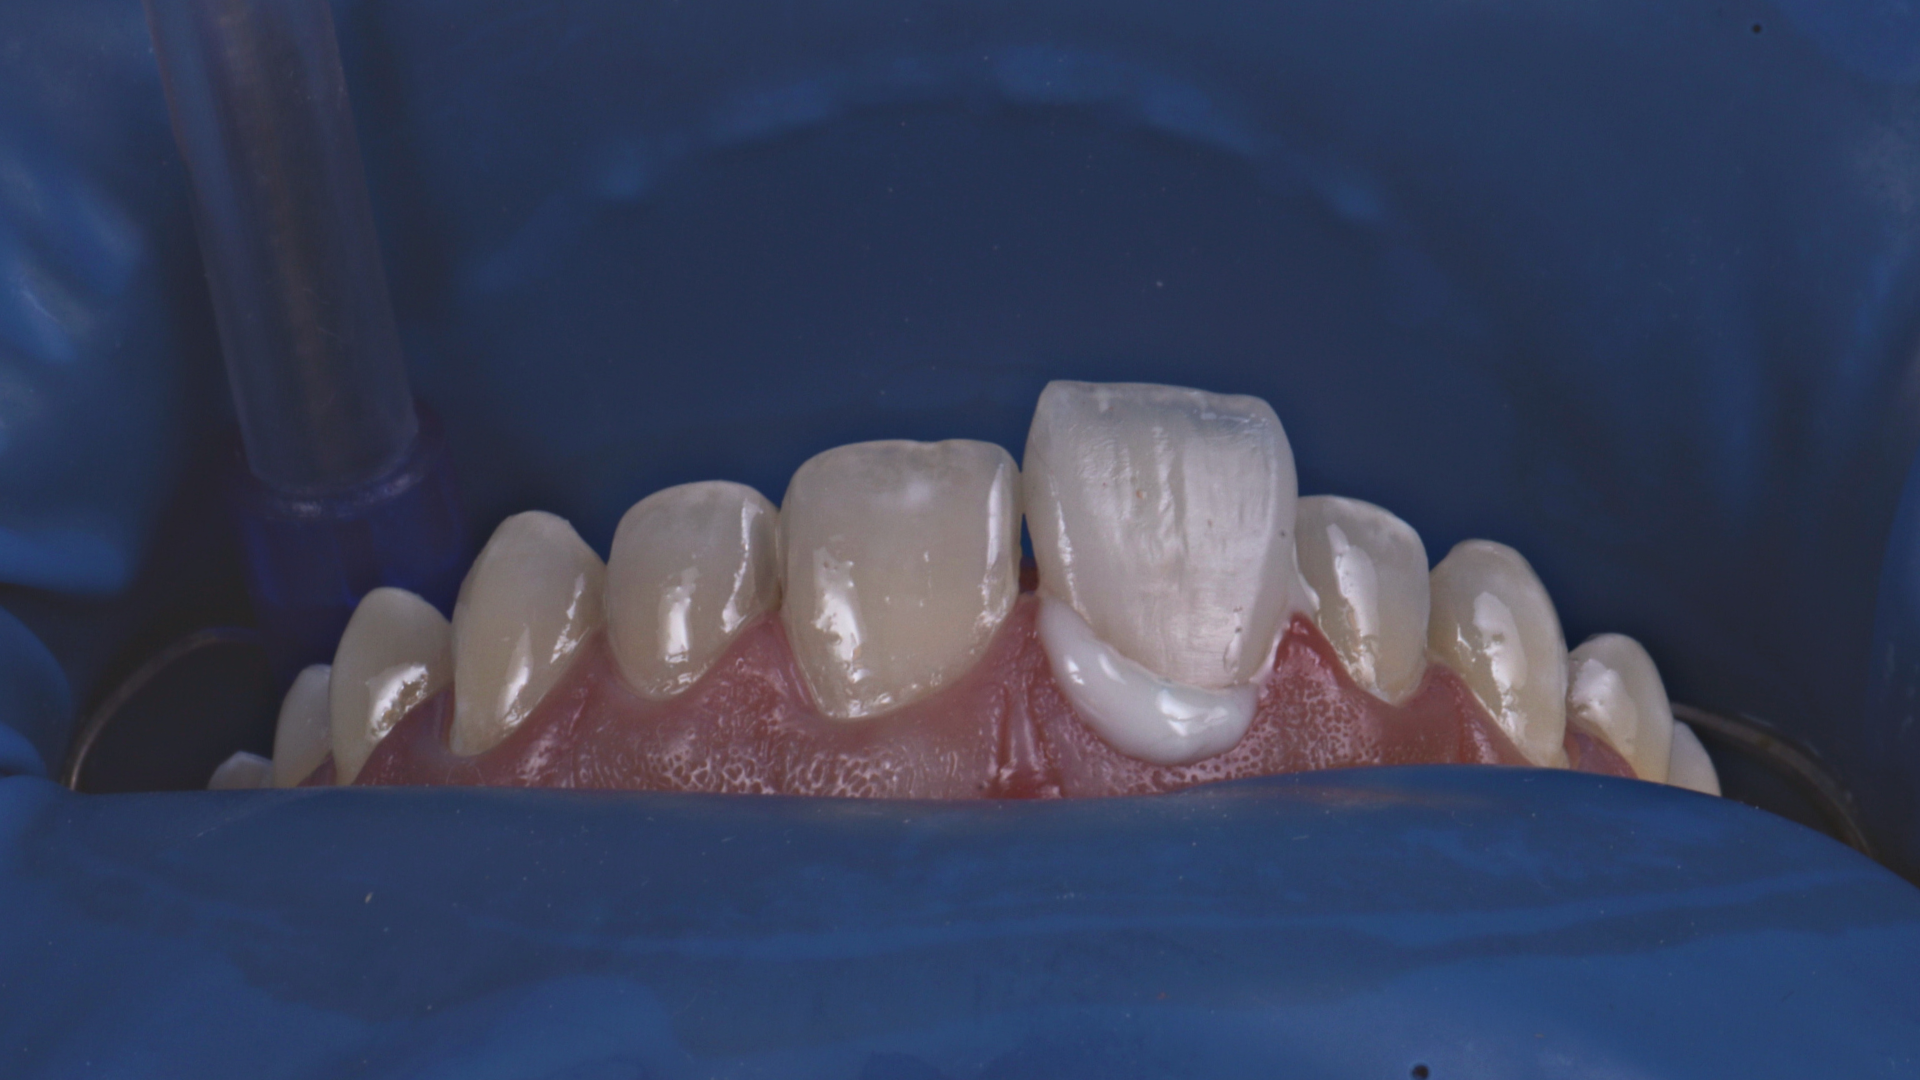

Full Veneers

Dictado por el Dr. Daniel Zabaleta, especialista en Rehabilitación Oral, Estética y Dentística con más de 20 años de experiencia y más de 19.000 casos clínicos exitosos.